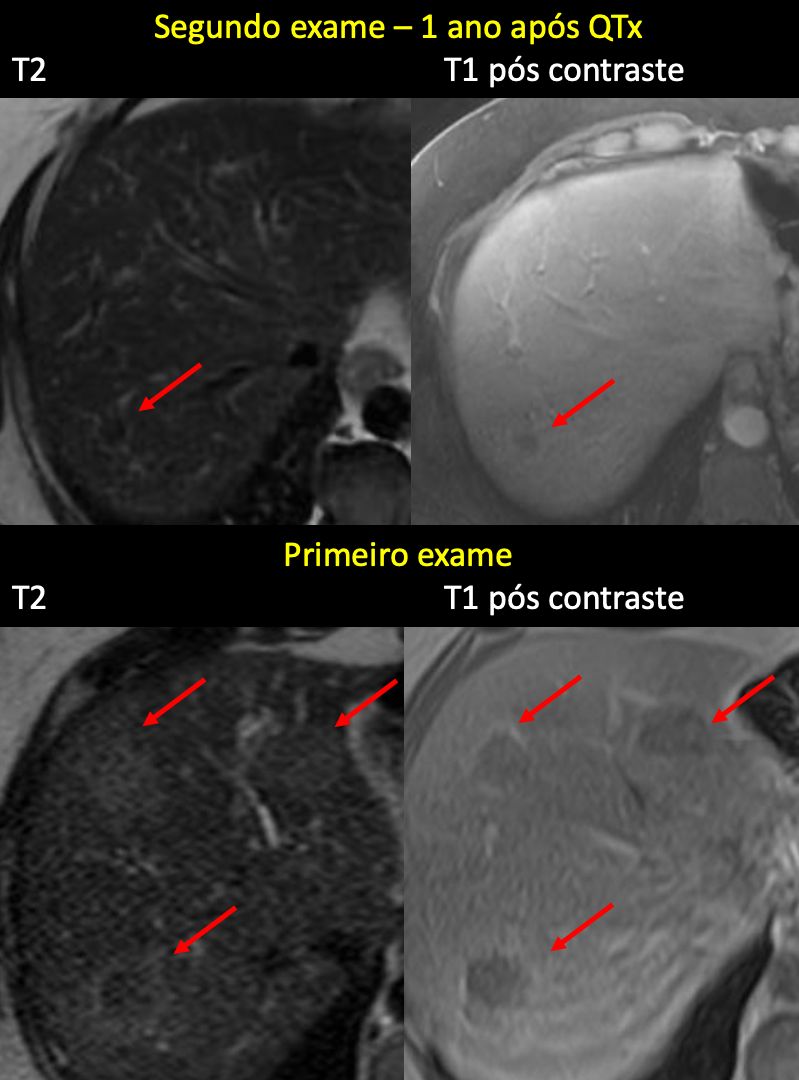

Diferenciação entre necrose, fibrose/cicatriz e tumor viável residual em metástases hepáticas de adenocarcinoma colorretal.

A avaliação evolutiva por ressonância magnética (RM) do fígado em pacientes com metástases hepáticas de adenocarcinoma de cólon após quimioterapia é um passo fundamental na radiologia oncológica moderna. Em muitos casos, a redução do tamanho da lesão não é suficiente para definir resposta completa, pois lesões residuais podem corresponder a tumor viável, fibrose/cicatriz pós-tratamento ou necrose.

Nesse contexto, a análise integrada das sequências de T2, difusão (DWI/ADC) e padrão de realce após contraste (incluindo fases tardias e, quando disponível, fase hepatobiliar com gadoxetato) é essencial para aumentar a precisão diagnóstica e apoiar o planejamento terapêutico, cirúrgico e o seguimento longitudinal.

Ponto-chave: a periferia da lesão é frequentemente a região mais importante na análise pós-tratamento, pois pode concentrar tecido tumoral viável residual mesmo quando o centro é predominantemente necrótico ou fibrótico.